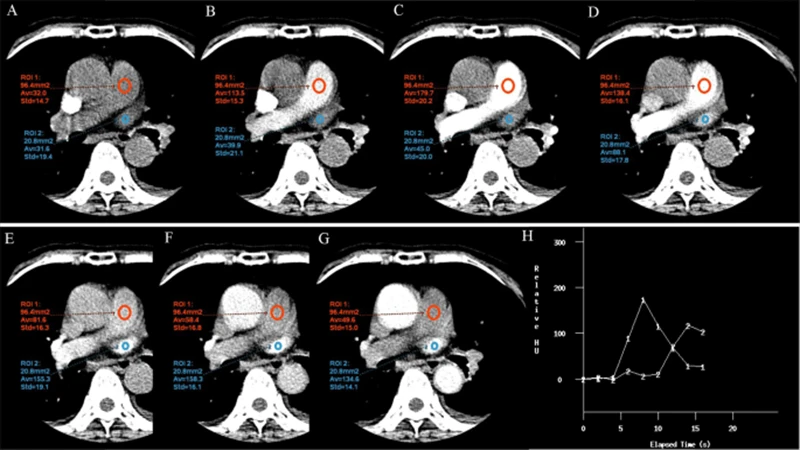

2. Scan Timing: This is the most critical element. The technologist must time the start of the scan perfectly to coincide with the moment the contrast-filled blood reaches the specific arteries or veins of interest. This "bolus tracking" is often done using a monitoring scan that detects when the contrast arrives at a target location.

A diagram illustrating bolus tracking, showing contrast injection followed by a timed scan as the contrast reaches the target artery.